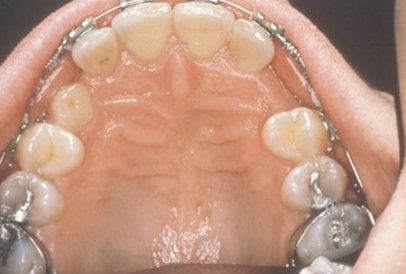

Normally, the maxillary cuspid teeth are the last of the “front” teeth to erupt into place. They usually come into place around age 13 and cause any space left between the upper front teeth to close tighter together. If a cuspid tooth gets impacted, every effort is made to get it to erupt into its proper position. The techniques involved to aid eruption can be applied to any impacted tooth in the upper or lower jaw, but most commonly they are applied to the maxillary cuspid (upper eye) teeth. Sixty percent of these impacted eyeteeth are located on the palatal (roof of the mouth) side of the dental arch. The remaining impacted eye teeth are found in the middle of the supporting bone, but are stuck in an elevated position above the roots of the adjacent teeth, or are out to the facial side of the dental arch.

In cases where the eyeteeth will not erupt spontaneously, the orthodontist and oral surgeon will work together to get these teeth to erupt. Each case must be evaluated on an individual basis, but treatment will usually involve a combined effort between the orthodontist and the oral surgeon. The oral surgeon will expose and bracket the impacted eyetooth.